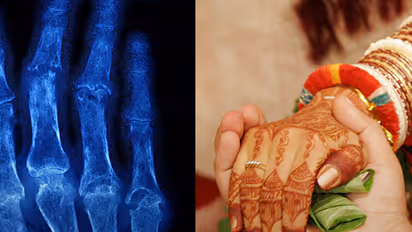

The State government has issued a notice in this regard asking the organisers of mass marriages not to accept any application which comes without x-ray copy of the couple. This action has been taken to prevent child marriages.

So far it was compulsory for the couple applying for the mass marriage to submit their birth certificate or a certificate from the doctor. But as many people were found to submit fake certificates, the government has taken action to ask the couple to submit a copy of x-ray.

A bone age study helps doctors estimate the maturity of a child's skeletal system. It's usually done by taking a single X-ray of the left wrist, hand, and fingers. Thus after the couple submits the document to the organisers of mass marriage, it is submitted to the Women and Child Welfare Department for their approval.

So far if the couple did not have birth or age certificate, they could get a certificate from any doctor. But in many cases, the certificates were found to be fake. Thus according to the Child marriages Prevention Act 6(2), the couple needs to take an x-ray at the Radiology department of the Government Hospital and get a certificate from the doctor concerned.